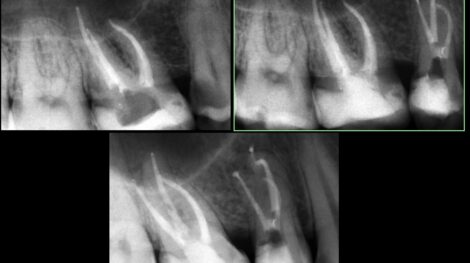

Leczenie zęba z dużą krzywizną korzenia